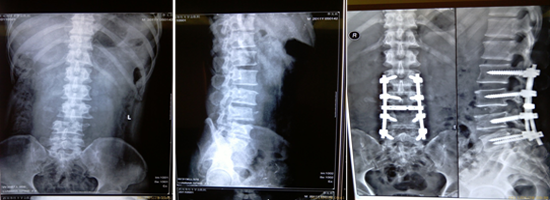

腰椎脫位切開(kāi)復(fù)位內(nèi)固定術(shù)